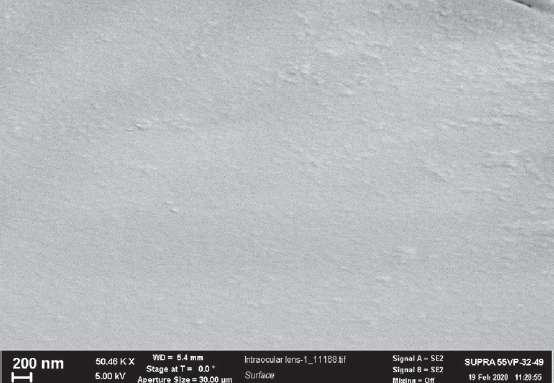

Fig. 5. Microphotography using a scanning electron microscope Supra 55VP (Carl Zeiss, Germany) of the explanted intraocular lens Oculentis. Small cracks and grooves are observed on the intraocular lens surface

Рис. 5. Микрофотография, полученная с помощью сканирующего электронного микроскопа Supra 55VP (Carl Zeiss, Германия) эксплантированной интраокулярной линзы Oculentis. Мелкие трещины и бороздки на поверхности линзы